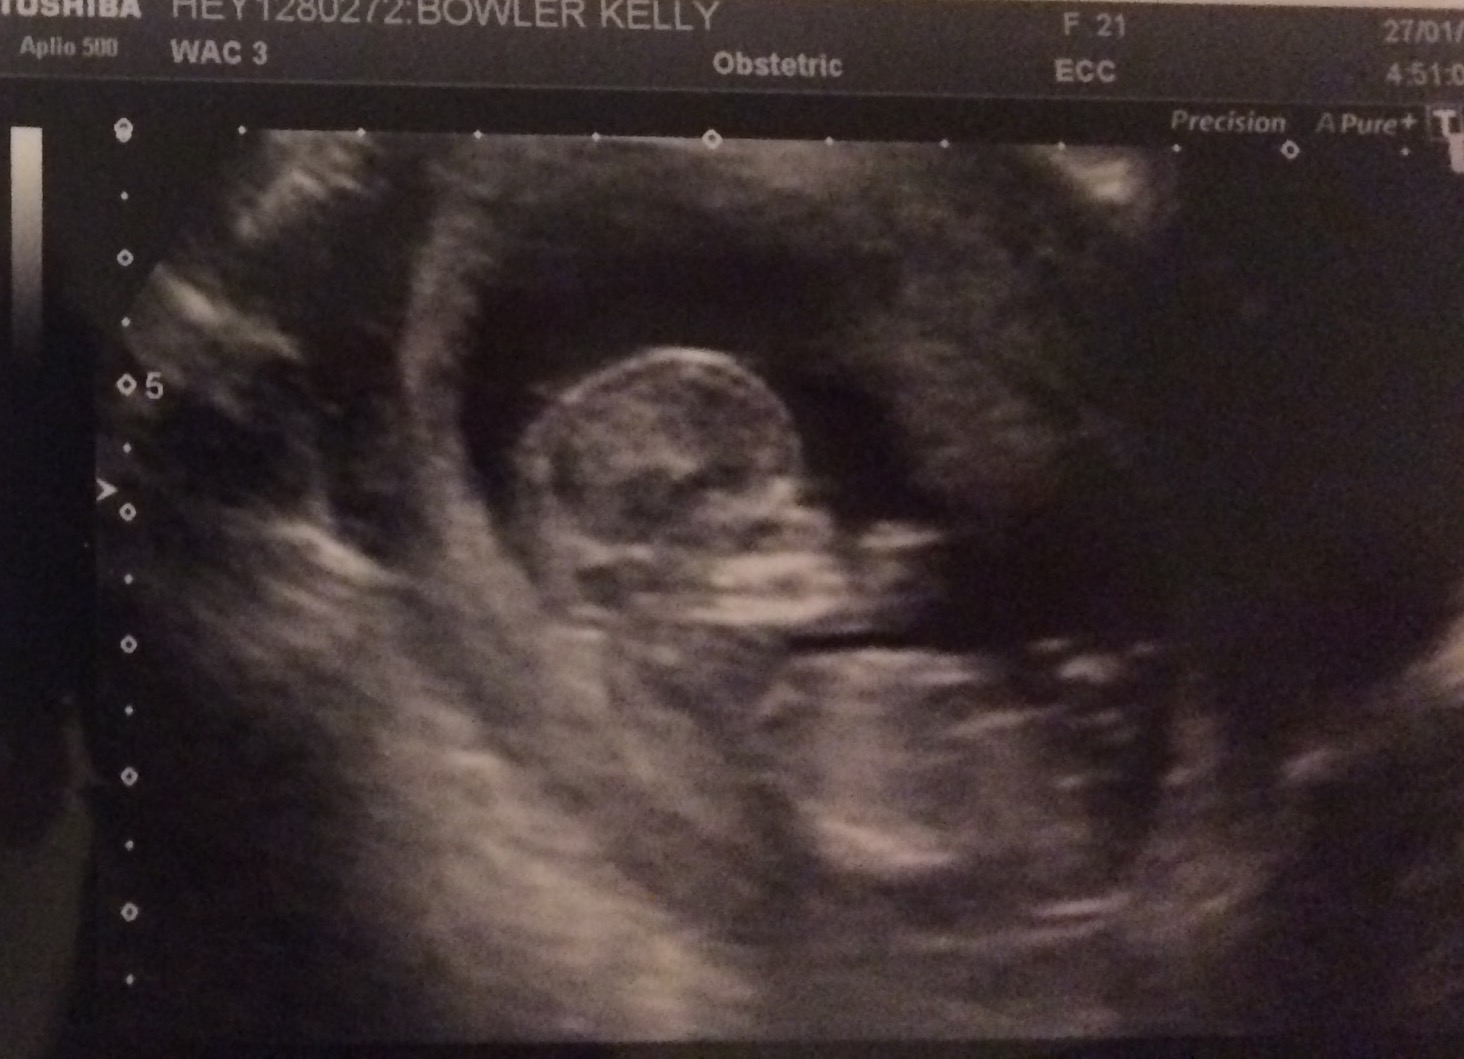

Hiya there, just wondered if anyone has any idea on if my 12 week scan photo looks like a boy or girl? I have heard of the shape of the nub and to me it looks like a boy! But im not sure if its in the right place and its actually the nub or not? Also i have read up about the skull theory that how you can tell from that? What do you all think ...

Attachment 35094